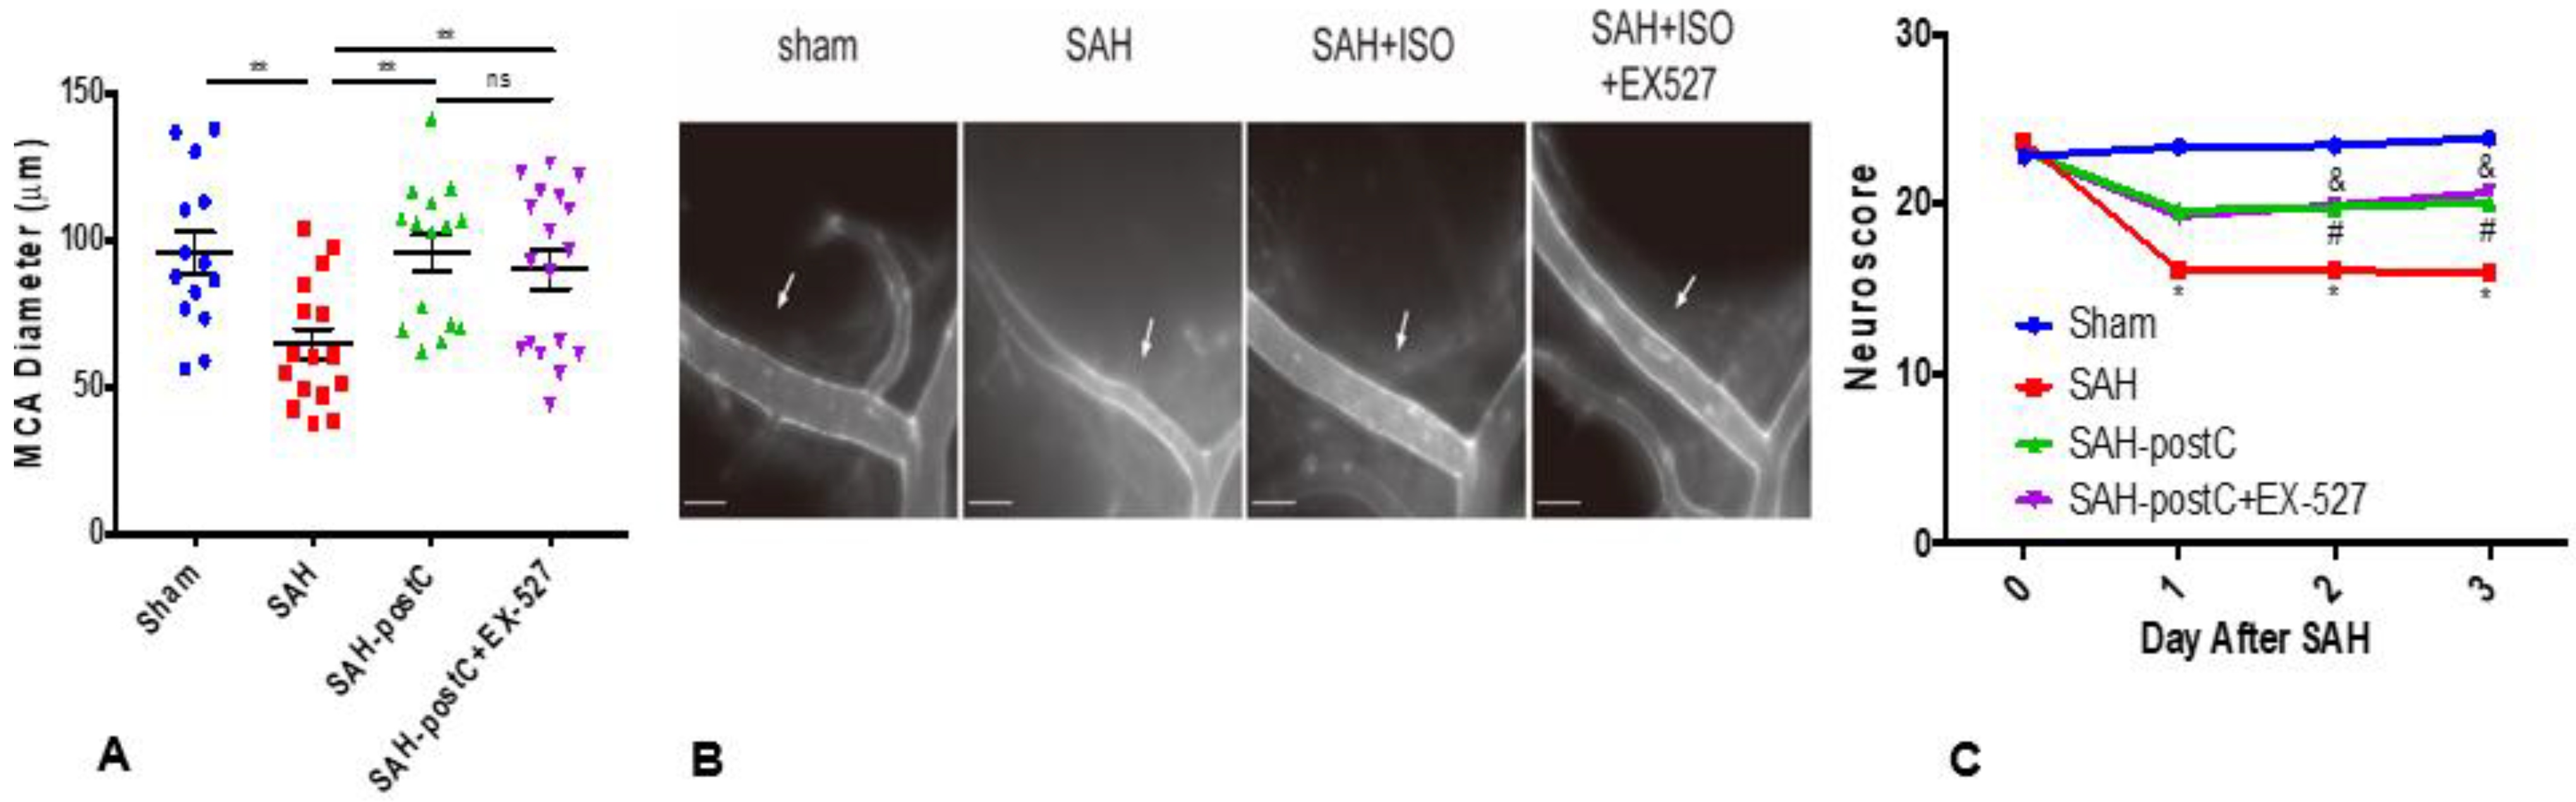

2.2. Isoflurane Conditioning with or without EX-527 Administration Attenuated SAH-Induced Large Artery Vasospasm and Improved Neurological Deficits in Wild Type Mice